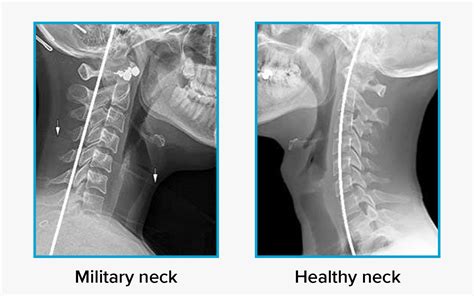

The human neck is marvelously designed with a natural, inward-curving arc known as the cervical lordosis. This gentle "C" shape is essential for supporting the weight of your head, acting as a shock absorber, and facilitating a full range of motion. However, modern lifestyle factors—ranging from prolonged screen time to poor posture—have led to an increasing prevalence of a straight cervical spine. Often referred to as "military neck" or cervical kyphosis in severe cases, the loss of this natural curvature can lead to a cascade of musculoskeletal issues. Understanding the causes, symptoms, and corrective measures for this condition is vital for anyone looking to maintain long-term neck health and spinal integrity.

What is a Straight Cervical Spine?

In a healthy neck, the cervical vertebrae align in a lordotic curve that distributes the load of your head evenly across the spine. When you have a straight cervical spine, this curvature flattens out, causing the neck to appear straight when viewed from the side on an X-ray or MRI. When this curve is lost, the weight of your head is no longer balanced, placing excessive stress on the muscles, ligaments, and intervertebral discs. This biomechanical imbalance is the root cause of many chronic neck pain complaints.

Diagnosis and Imaging

If you suspect you have a straight cervical spine, a physical examination by a chiropractor, physical therapist, or orthopedic specialist is the first step. They will check for muscle imbalances and range of motion restrictions. However, to confirm the loss of curvature, medical imaging is necessary:

• Lateral Cervical X-ray: The most common method to view the curvature of the spine from a side profile.